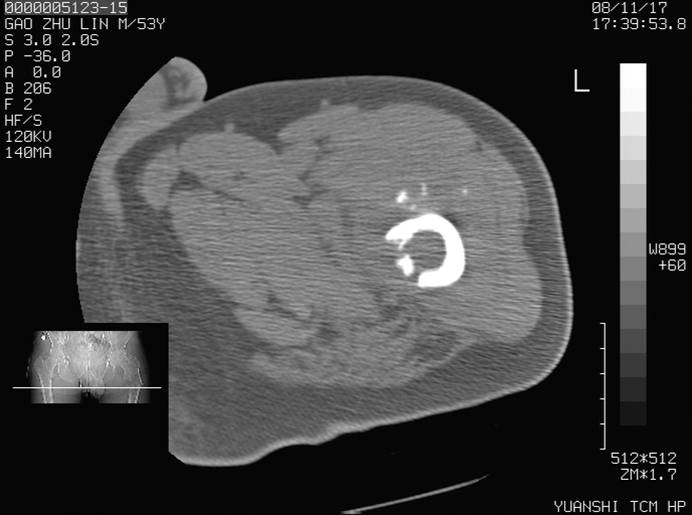

标题: CT16696:M53Y,左股骨上段骨折。 [打印本页]

标题: CT16696:M53Y,左股骨上段骨折。

左股骨上段外伤1个小时,左股骨上段疼痛。村医以腰椎间盘病变给以按摩及理疗数天。

图像不太清楚,左股骨上段外伤性骨折?病理性骨折?

左股骨上段粉碎性骨折

左股骨上段粉碎性骨折;建议上传骨窗看看是不是病理性的啊!

左股骨上段粉碎性骨折,不排除病理性骨折可能。

考虑骨肉瘤伴病理骨折

考虑:骨肉瘤伴病理骨折.

病理性骨折,考虑转移所致.